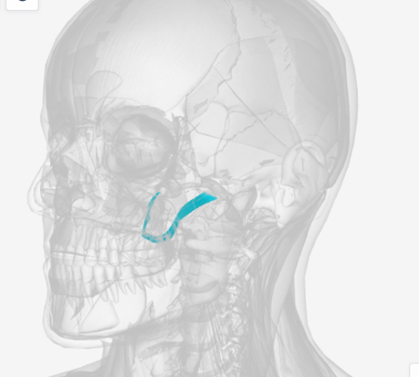

Tensor veli palatini

origin is on the sphenoid bone, coursing down to a tendon wrapping down around the pterygoid hamulus (of the sphenoid), then directed medially to the palatal aponeurosis; function is to dilate the Eustachian tube

Tensor Veli Palatini

|  |  |

Tensor veli palatini

C

Pterygoid hamulus

D